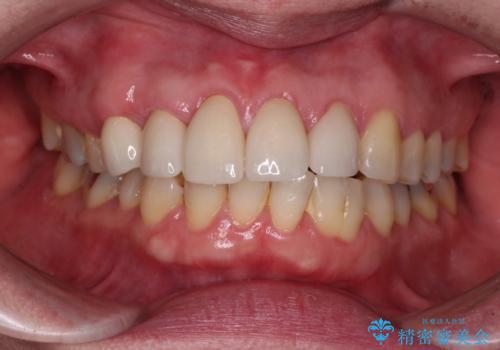

八重歯と形の悪い前歯 矯正治療とセラミック治療